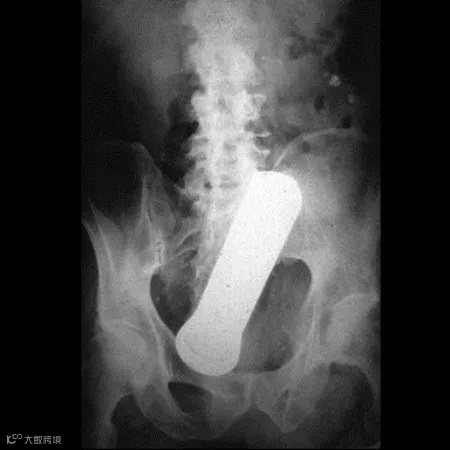

玻璃棒▽

扳手▽

擀面杖▽

十斤重的哑铃▽

钥匙▽

手电筒▽

鸡蛋▽

巴斯光年▽

这些本不该出现在肛门内的东西,总有人会“一不小心”塞进去了,这对菊花来说是很大的一种伤害。